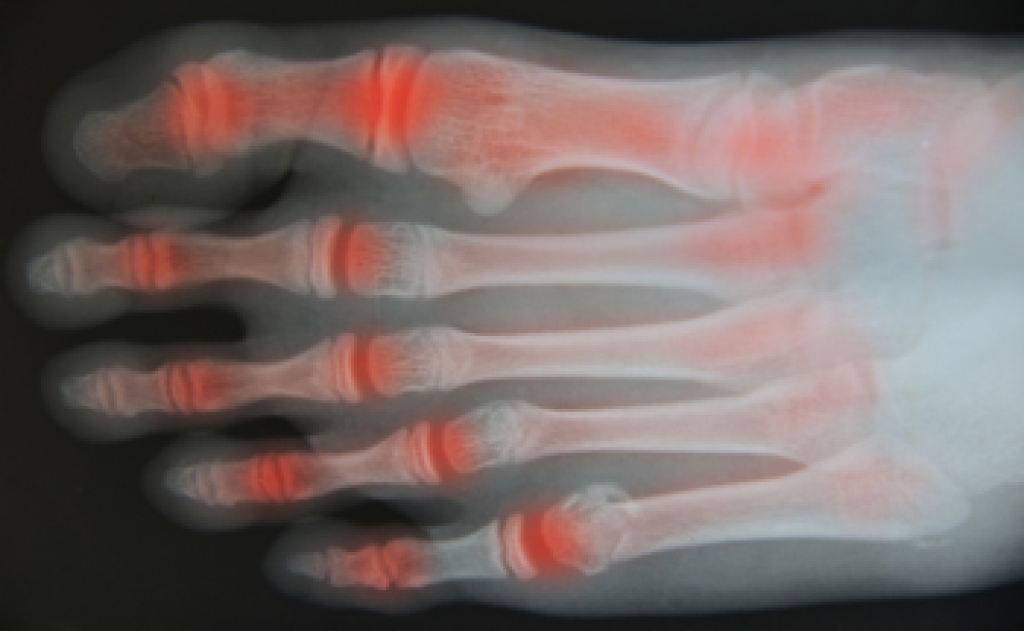

What Are the Symptoms?

- Mild to moderate bruising

- Limited mobility

- Swelling

- Discoloration of the skin (depending on severity)